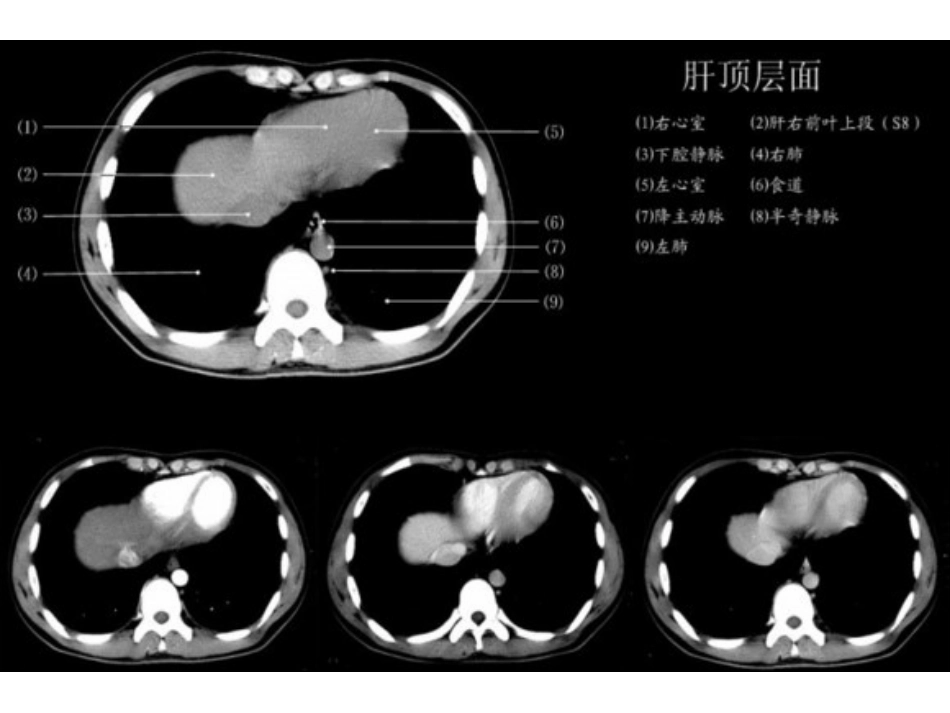

上腹部CT-各个层面VIP免费

上腹部CT-各个层面